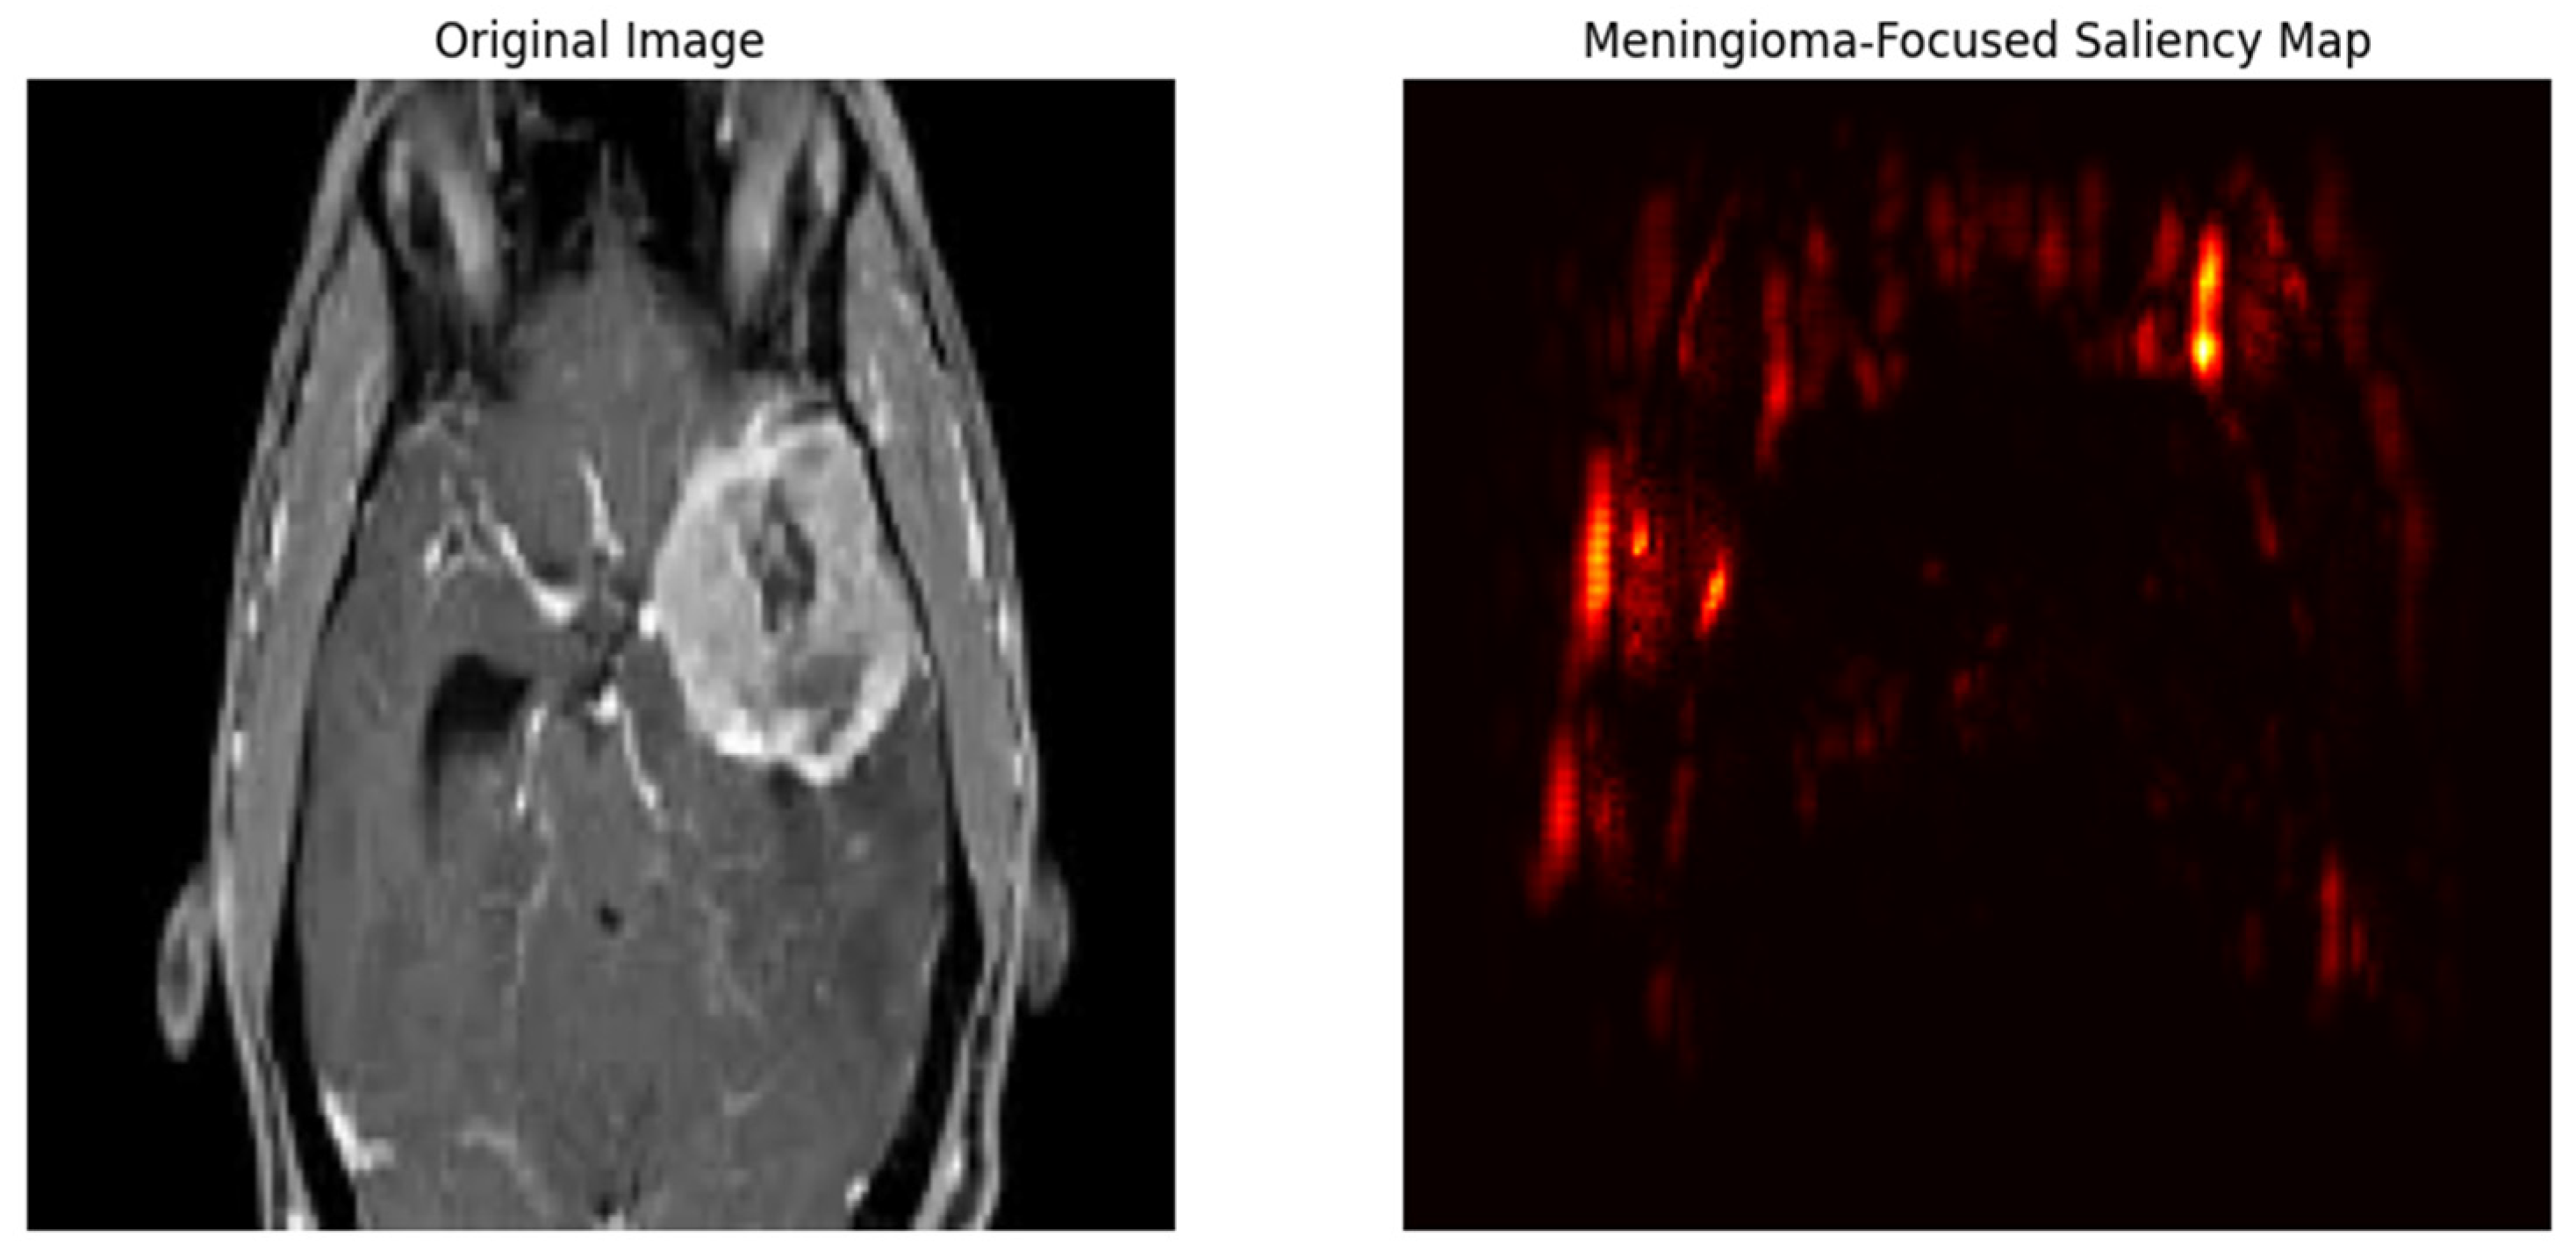

- Saliency maps: We also generated saliency maps to pinpoint the specific regions within the brain scans that most significantly influence the model’s output [31]. This helps us understand which parts of the image hold the most weight for the model’s decision-making process.

- Feature interpretation: We utilized gradient-based attribution methods like Integrated Gradients and Guided Backpropagation [31]. These methods helped us visualize the features the model learned from the brain scan images and how they contribute to the final classification (tumor type or healthy).